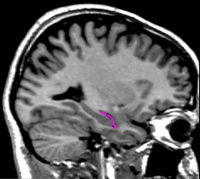

| General Description The amygdala is located in the medial temporal lobe. It has a rounded shape and is situated anterior and superior to the hippocampus. Anteriorly, the amygdala borders the entorhinal/perirhinal temporopolar cortex. Superiorly, it borders the basal forebrain and the choroidal fissure. Medially, the amygdala borders the entorhinal cortex (in its anterior most tip) as well as the subarachnoid CSF of the medial temporal surface. Its lateral borders are the temporal horn of the lateral ventricle as well as (more rostrally) the white matter core of the temporal pole. Inferiorly, it borders with the entorhinal cortex (PHa), and more posteriorly, the hippocampus. Its caudal border is the hippocampus. | |

|  | Continue to scroll the sagittal image medially. As you do, the size of the ILV will decrease, and the grayness of the amygdala will become more pronounced. When the ILV is very thin, and the amygdala and hippocampus look as if they will touch soon, draw a sulci line from the superior to the inferior border of the ILV, right in the middle of the ventricle, separating the hippocampus from the amygdala. Continue to move medially, and continue to draw sulci lines bisecting the ILV. Draw sulci lines only on slices where you can see the border between the hippocampus and the amygdala. |

|  | As you move more medially, this differentiation will be difficult to see. There are two clues you can use to guide you as you draw these lines. First, the ILV will appear as dark pixels. You will most likely see part of the ILV superior to the hippocampus. You should also see a very tiny dark dot at the inferior-anterior border of the hippocampus. This is part of the ILV, specifically its anterior-most tip. Using the general shape of the ILV you observed in more lateral sagittal views, draw a sulci line from the most superior part of the ILV you can see to its anterior-most tip. A second clue to the division between the hippocampus and amygdala is that the superior border of the hippocampus includes the fimbria. This will appear as a white line just below the ILV. If this can be seen, it can be used as a guide; draw your sulci line along the black pixels that are above this white line. |